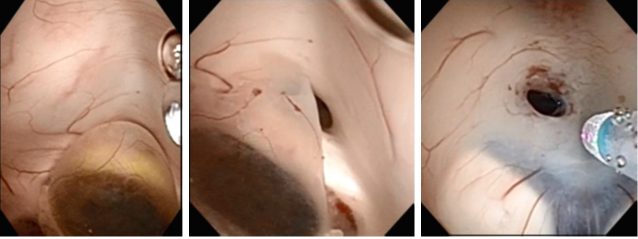

Figure 3 Endoscopic image before tearing the cyst (a) after tearing the cyst, (b) Endoscopic image of the third ventriculostomy.